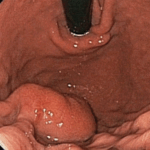

Boerhaave Syndrome: An Updated Review with an Emphasison Endoscopic Treatments

Introduction Spontaneous rupture of the esophagus is also known as Boerhaave syndrome after the Dutch physician who first described it in 1724.1 Historically, Boerhaave syndrome was considered uniformly fatal. Boerhaave […]